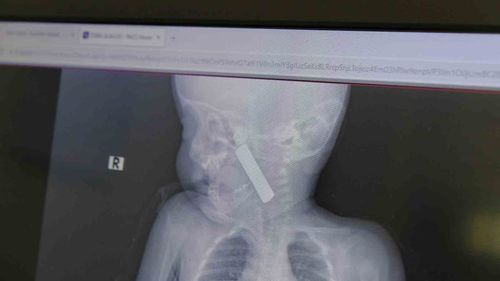

Karaman'da 6 aylık E.A.’nın boğazına kaçan kumanda pili, Çocuk Cerrahisi Uzmanı Doç. Dr. Mehmet Uysal tarafından çıkarıldı; 24 saat takip sonrası taburcu edildi.

Karaman'da 6 aylık bebeğin boğazından kumanda pili ameliyatla çıkarıldıOlayın gelişimiKaraman Eğitim ve Araştırma Hastanesi acil servisine kusma şikayetiyle getirilen 6 aylık E.A. isimli kız bebekte yapılan muayene ve tetkiklerde, boğazına kumanda pili kaçtığı tespit edildi.Bebekte solunum sıkıntısı gözlenirken hastanın oksijen…